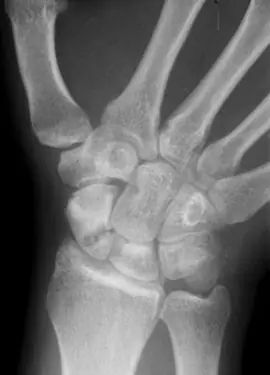

¿Por qué se ven los huesos con los rayos X?Una radiografía es una fotografía del interior del cuerpo, más concretamente de los huesos. Pero ¿cómo es eso? ¿Cómo se fotografía “lo de dentro” sin captar “lo de fuera”?

Pues con ayuda de los rayos X —llamados inicialmente rayos Roetgen en honor a su descubridor— que son una radiación electromagnética cuya frecuencia de vibración se encuentra entre la luz ultravioleta y los rayos gamma emitidos en las reacciones nucleares.

Su alta frecuencia, de 30 a 3.000 PHz (1 PHz = 1·1015 Hz) y su corta longitud de onda (entre 10 y 0,1 nanómetros) le confieren un alto grado de penetración e ionización.

Debido a esa alta capacidad de penetración, si radiamos un cuerpo humano con rayos X, éstos lo atravesarán sin problema. Pero dependiendo del tipo de tejido atravesado lo harán de forma más o menos amortiguada. Así, colocando una placa fotográfica de manera que recoja los rayos tras su paso por el cuerpo, es posible obtener una imagen en la que prácticamente sólo se aprecian los huesos, ya que el resto de tejidos son virtualmente transparentes a este tipo de radiación.

Por ello son especialmente útiles para la localización de roturas o malformaciones óseas, así como para la detección de cuerpos extraños en el organismo.

Pero debido a su alto poder ionizante —que modifica las moléculas a su paso— resultan gravemente perjudiciales en altas dosis, pues producen cambios en el ADN que podrían devenir en cáncer, por lo que no deben realizarse con frecuencia, o en malformaciones embrionarias, por lo que no se deben realizar radiografías a gestantes.

Por ello los médicos o el personal técnico-sanitario que las realiza, se protegen tras cabinas de plomo mientras se realiza la exposición, pues el metal los protege al apantallar la radiación.